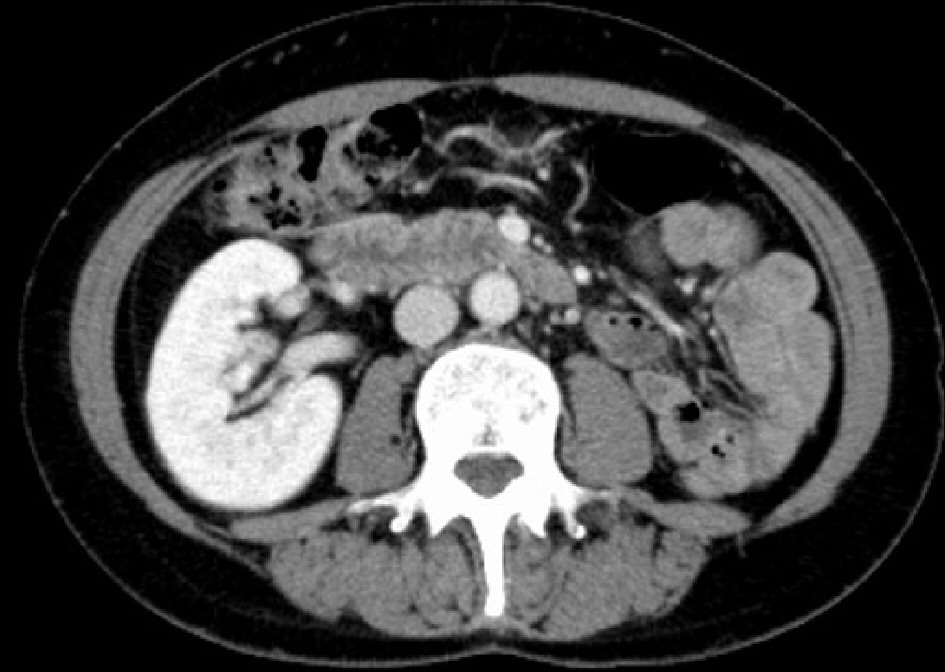

A 52-year-old nulligravida woman presented with 1 month of intermittent vaginal spotting 2 years after menopause. She had no history of smoking or medical diseases. Her family history included an uncle who died of gastric cancer. The patient had no history of in-utero diethylstilbestrol (DES) exposure. A previous cervical smear was unremarkable 11 months ago. Speculum examination revealed a single cervix and a 2-cm mass on the cervix, which showed macrocarcinoma of the cervix. No parametrial or vaginal involvement was detected. The biopsy specimen from the tumor on the uterine cervix revealed CCC. The tumor was comprised of atypical cells displaying enlarged nuclei with prominent nucleoli and clear-to-eosinophilic cytoplasm; the cells also displayed papillary structures with a hobnail-like appearance. Immunohistochemical staining showed that the tumor cells were positive for HNF-1β and napsin A. Laboratory data revealed that the patient’s squamous cell carcinoma antigens, carbohydrate antigen (CA) 125 levels, and CA19-9 levels were negative. Magnetic resonance imaging (MRI) of her pelvis showed uterine didelphys and a mass measuring 1.5 × 2.0 cm located in the left endocervix that had not invaded the parametria, adjacent organs, or regional lymph nodes. Furthermore, a left-sided obstructed hemivagina was observed (Fig. 1). Although an enhanced computed tomography (CT) scan of the chest and abdomen did not reveal evidence of lymph node metastasis or distant metastasis, left renal agenesis was observed (Fig. 2). Based on the findings of left renal agenesis, uterine didelphys, and obstructive hemivagina, we diagnosed her with OHVIRA syndrome and CCC of the cervix and classified her as International Federation of Gynecology and Obstetrics stage IB1.

![]() Click for large image | Figure 2. CT scan shows the absence of the left kidney. CT: computed tomography. |